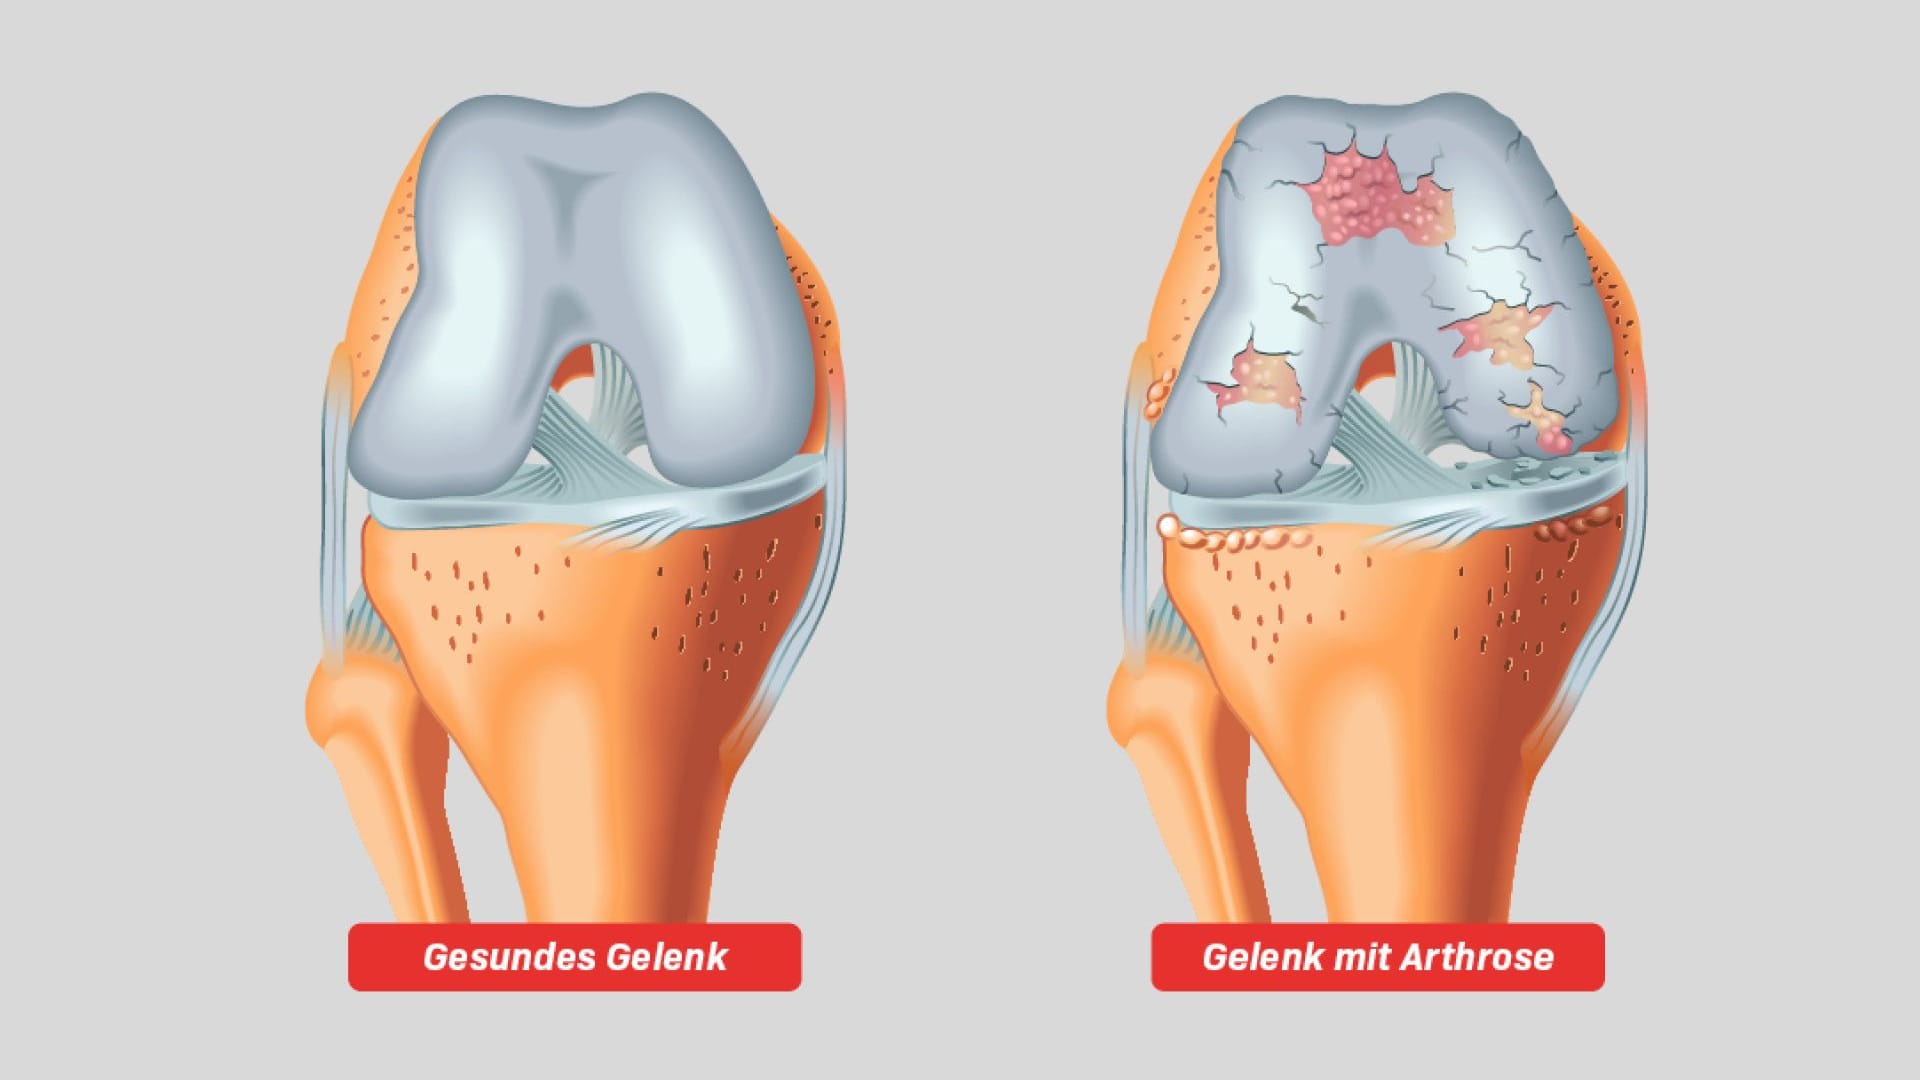

Arthrose gilt als eine Verschleißkrankheit der Gelenke, bei der sich der Knorpel an den Gelenken abnutzt. Dieser Knorpel bildet in der Regel eine Schutzschicht, die sich zwischen zwei Knochenenden befindet und verhindern soll, dass die Knochen aneinander reiben.

Zudem dient der Knorpel als eine Art Stoßdämpfer, der die Belastung gleichmäßig auf das Gelenk verteilt. Nutzt sich der Knorpel im Laufe der Jahrzehnte ab, reiben schließlich die blanken Knochen ungeschützt aneinander. Dies führt zu starken Schmerzen und Entzündungen. Arthrose kann dabei in fast jedem Gelenk entstehen.

Unbehandelt kann die Abnutzung der Gelenkknorpel ungebremst voranschreiten und Entzündungen zur Folge haben. Durch das Aneinanderreiben der Knochen sammelt sich Knorpelabrieb, der zu Entzündungen führt. Es kann zu dauerhaften Schmerzen und eingeschränkter Beweglichkeit kommen.